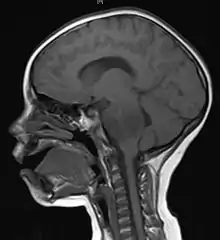

Imaging

Medical imaging plays a central role in the diagnosis of brain tumors. Early imaging methods – invasive and sometimes dangerous – such as pneumoencephalography and cerebral angiography have been abandoned in favor of non-invasive, high-resolution techniques, especially magnetic resonance imaging (MRI) and computed tomography (CT) scans,[39] though MRI is typically the reference standard used.[40] Neoplasms will often show as differently colored masses (also referred to as processes) in CT or MRI results.

This is because these tumors disrupt the normal functioning of the BBB and lead to an increase in its permeability. More recently, advancements have been made to increase the utility of MRI in providing physiological data that can help to inform diagnosis and prognosis. Perfusion Weighted Imaging (PWI) and Diffusion Weighted Imaging (DWI) are two MRI techniques that reviews have been shown to be useful in classifying tumors by grade, which was not previously viable using only structural imaging.[41] However, these techniques cannot alone diagnose high- versus low-grade gliomas, and thus the definitive diagnosis of brain tumor should only be confirmed by histological examination of tumor tissue samples obtained either by means of brain biopsy or open surgery. The histological examination is essential for determining the appropriate treatment and the correct prognosis. This examination, performed by a pathologist, typically has three stages: interoperative examination of fresh tissue, preliminary microscopic examination of prepared tissues, and follow-up examination of prepared tissues after immunohistochemical staining or genetic analysis.